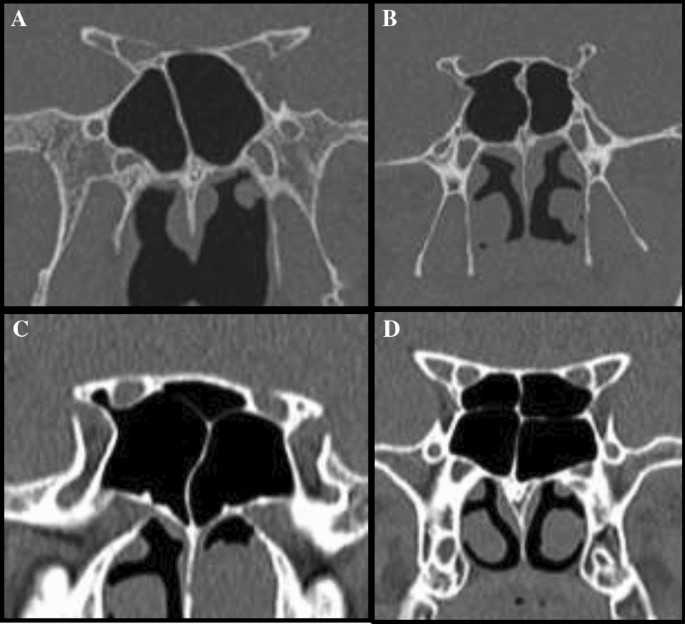

A Presellar Type Of Sphenoid Sinus B Postsellar Sphenoid Sinus In Download Scientific Diagram

Example Of Segmentation Of Sphenoid Sinuses From A Head Ct Scan Download Scientific Diagram

Assessment Of Variations In Sphenoid Sinus Pneumatization In Indian Population A Multidetector Computed Tomography Study Semantic Scholar

Cone Beam Computed Tomography Analysis Of Sphenoid Sinus Pneumatization And Relationship With Neurovascular Structures Springerlink